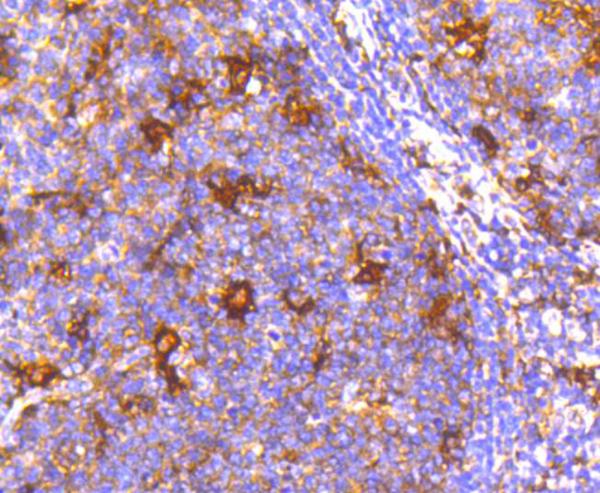

BCMA, Monoclonal Antibody (Cat# AAA27969)

BCMA, Monoclonal Antibody (Cat# AAA27973)

BCMA, Monoclonal Antibody (Cat# AAA27974)

CD204, Monoclonal Antibody (Cat# AAA11862)